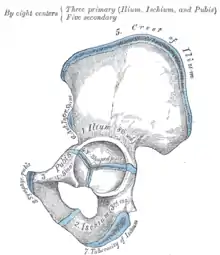

Muscles connecting the upper extremity to the vertebral column. Left iliac crest is labeled in red. Plan of ossification of the hip bone

Plan of ossification of the hip bone The Obliquus internus abdominis